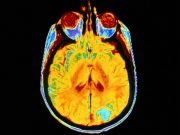

AI Model Detects Normal, Abnormal Findings on Brain MRI

Model, which was trained on data from one institution and tested on data from a second institution, had area under the curve of 0.78